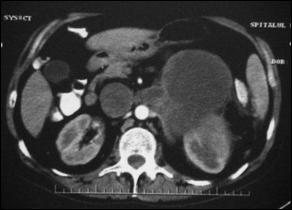

Fig.5. Feocromocitom suprarenalian drept - aspect TC. |